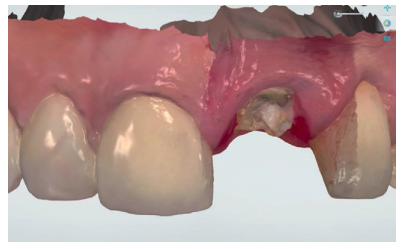

Utilizando el escáner 3Shape®, se realizó un pre-escaneado intraoral, primero con la corona dentosoportada colocada, para obtener la anatomía del incisivo central, y después sin ésta, escaneando así el perfil de emergencia del resto radicular; se informó al laboratorio de la modificación del perfil critico, corrigiendo así la recesión existente respecto al 1.1 (Figuras 5-7). Este escaneado sirvió a su vez para la toma de color del futuro provisional7,8. El archivo STL fue enviado al laboratorio protésico para elaborar la prótesis provisional tipo Maryland, en polimetil-metacrilato (PMMA), con dos apoyos en los bordes incisales de los dientes adyacentes para asegurar su correcto posicionamiento que, según la planificación previa, serviría como diente provisional, así como de guía quirúrgica para la inserción del IOI en la posición protésica idónea, evitando así posibles problemas futuros a nivel protésico o en la integridad de los tejidos blandos y duros de la región vestibular (Figuras 8 y 9).

Tras conseguir un volumen de tejido óptimo mediante el manejo del provisional (Figura 17), se realizó un primer escaneado del maxilar con la corona provisional atornillada para obtener la anatomía (Figura 18) y, posteriormente, un segundo escaneado sin la misma, registrando de forma precisa los contornos gingivales y el perfil de emergencia conseguido (Figura 19), así como la posición del implante mediante el scan body (Figuras 20 y 21). Para un correcto duplicado del perfil de emergencia, se procedió a escanear la corona provisional fuera de la boca (Figuras 22 y 23), evitando tener que realizar la técnica clásica de un transfer individualizado17. Estos registros fueron enviados al laboratorio protésico, el cual diseñó una estructura metálica sinterizada postmecanizada (Figura 24). Una vez realizada de forma satisfactoria la prueba de la estructura (Figura 25), se tomó el color de la restauración (A2 guía VITA) mediante un filtro de luz polarizada (Figura 26). Estos registros se enviaron de nuevo al laboratorio protésico para la finalización de la corona implantorretenida sobre los modelos impresos (Figuras 27 y 28). Previo a la colocación de la corona definitiva, se comparó el perfil de emergencia de la corona provisional con la definitiva, viendo la similitud entre ellas (Figura 29), consiguiendo así preservar los perfiles mantenidos desde el día de inicio del tratamiento.